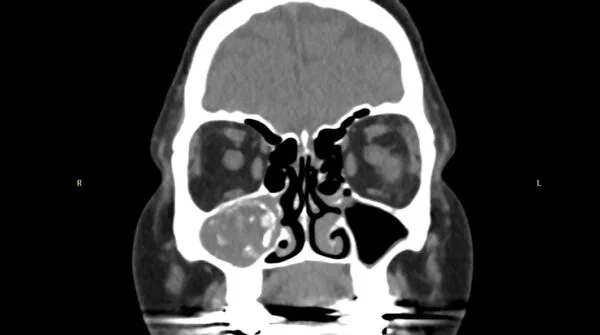

Radiology

- Heterogeneous opacities in CT images

- Bone erosion and deformity in severe cases

- Characteristic CT signs: Serpiginous areas of increased attenuation on a computed tomography (CT) scan, unilateral predominance

- Hyperdense, calcified opacity on CT imaging (also called as starry sky pattern)